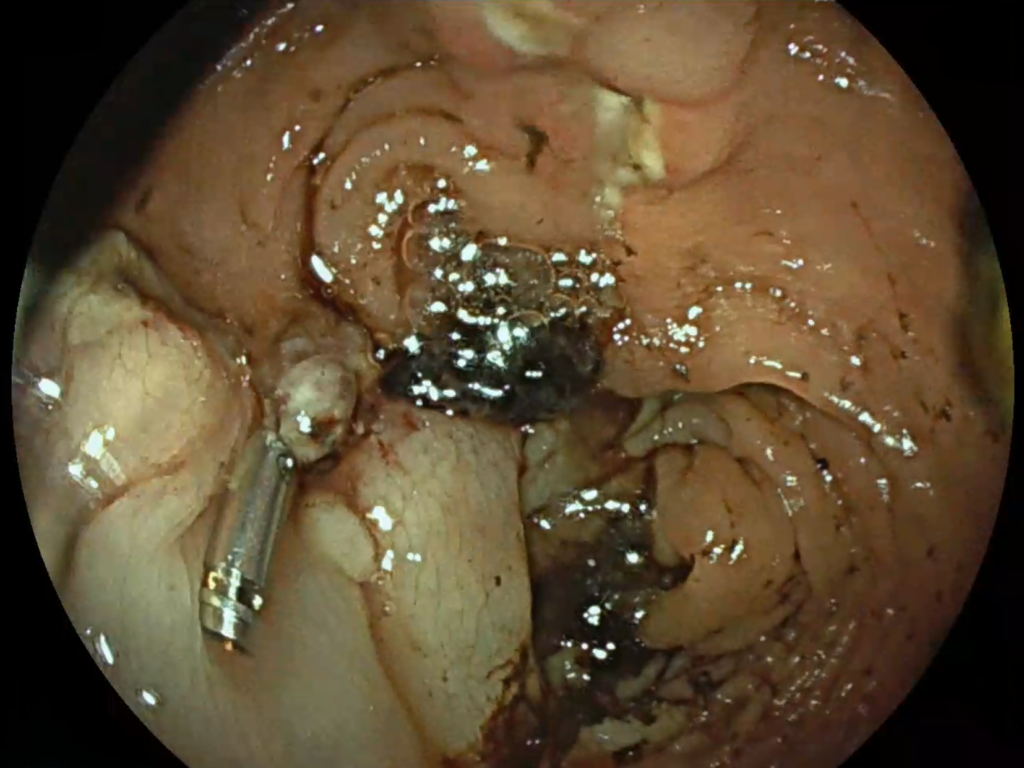

Inițial, evoluția postoperatorie a fost favorabilă. Totuși, pacientul a dezvoltat o hemoragie digestivă inferioară, gestionată prompt prin hemostază endoscopică de urgență de către dr. David Marica, în contextual nevoii constante de hemodializă.